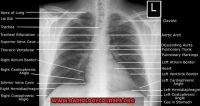

Radiologycourses.org Tips and Hints for the first and Second FRCR anatomy and physics exams. Gallery

FRCR preparation course Dubai